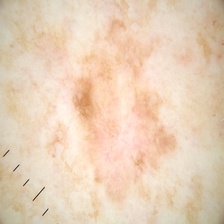

malignant

107.jpg

224x224px